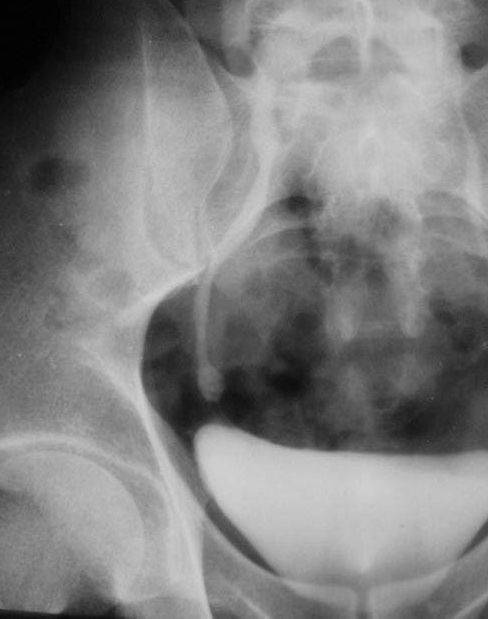

照片名称:膀胱癌5

照片名称:膀胱癌

照片名称:膀胱癌2

照片名称:膀胱癌4